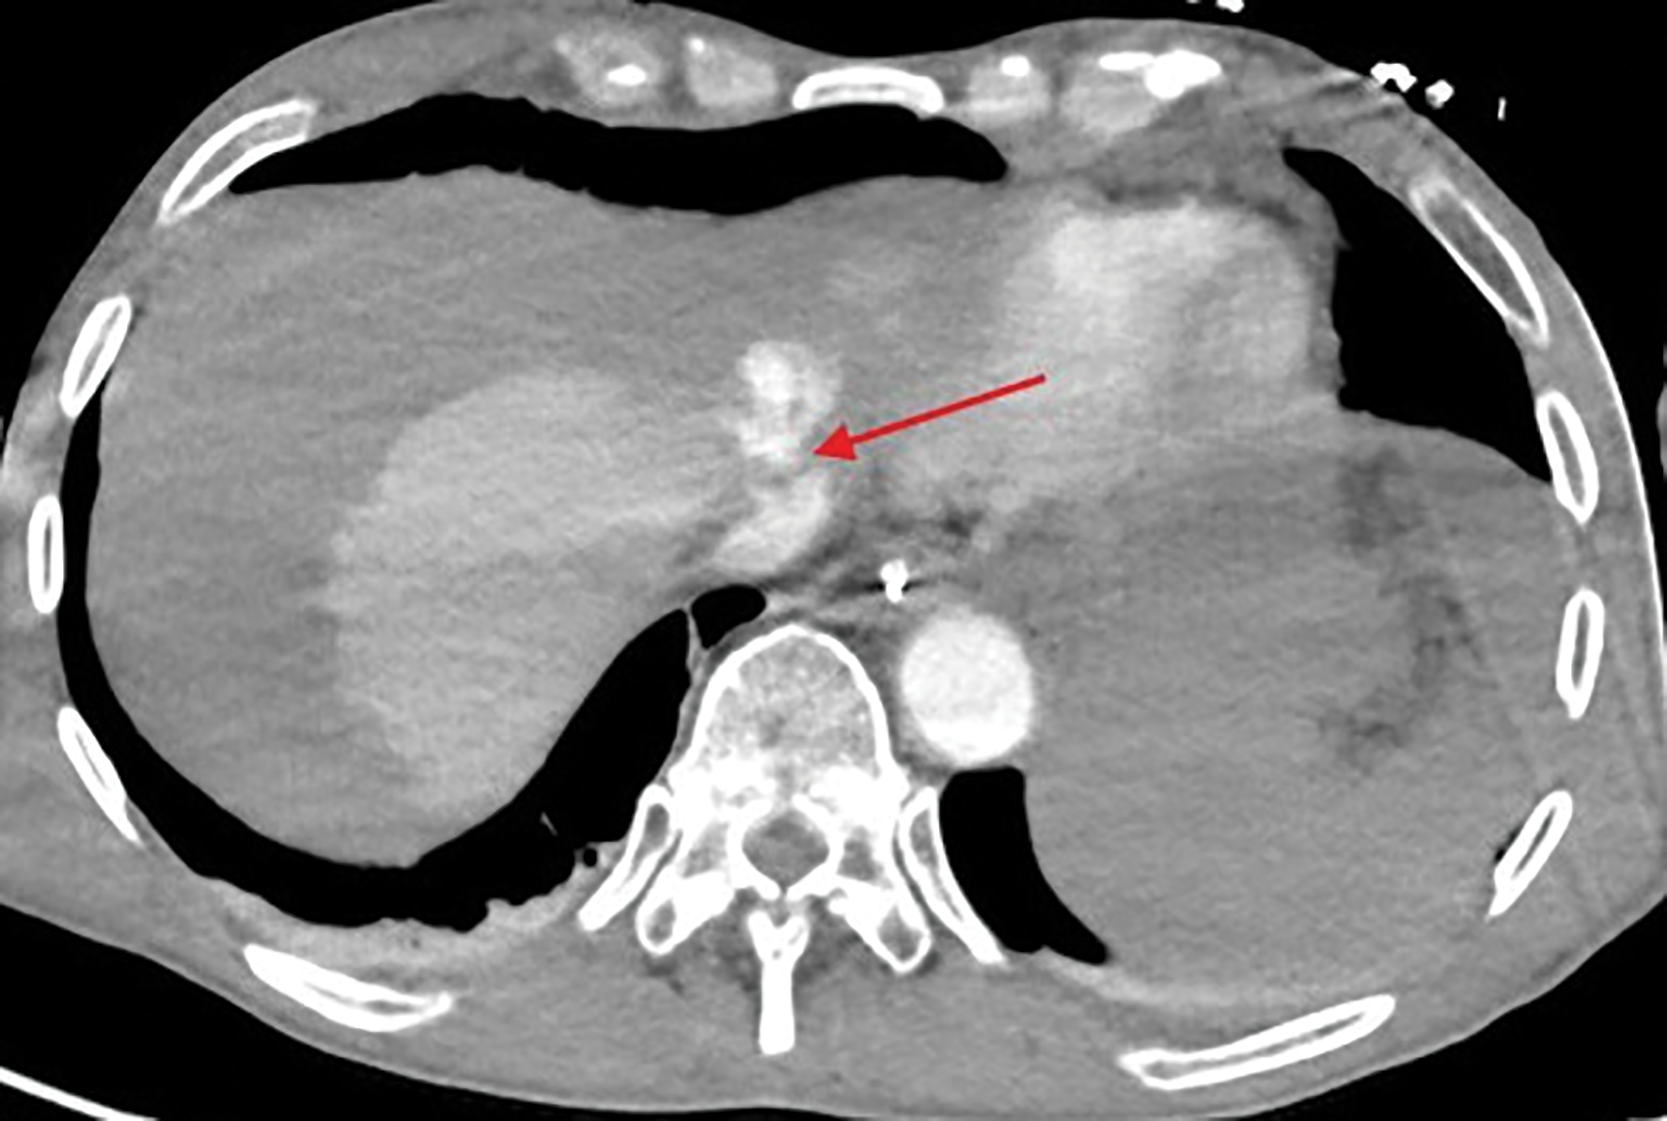

The bleeding was most likely originating from the lacerated left hepatic vein, at the confluence with the vena cava (Figure 2, red arrow).

Figure 2

Lacerated left hepatic vein at the confluence with the vena cava.